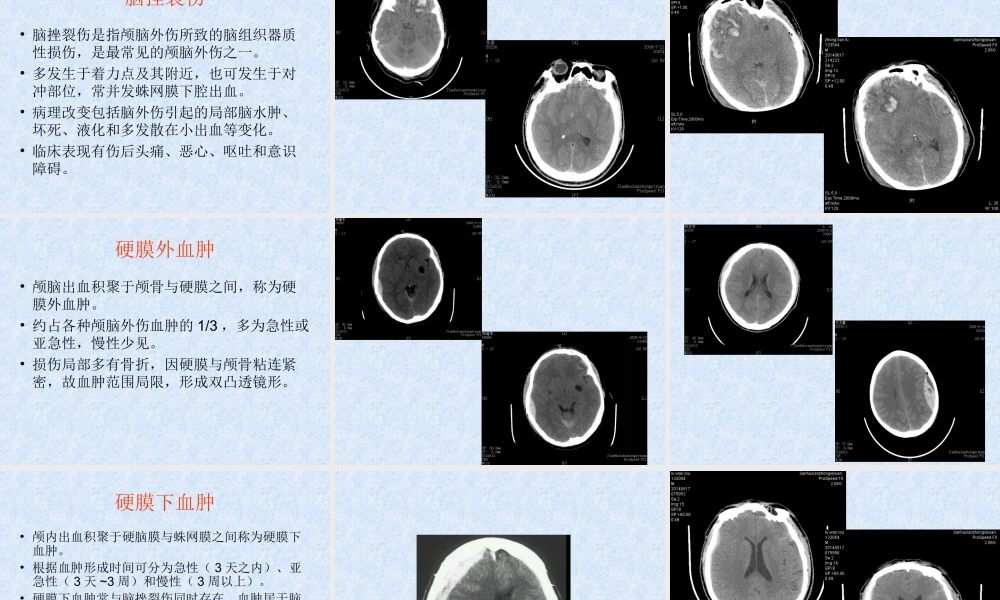

临床急诊的影像学检查与诊断建湖中医院影像科刘玉兵序言•急诊的范畴非常广泛,涉及内、外、妇、儿等临床各科,急诊病情急重,变化迅速。急诊接诊医师对急诊病人的诊治途径常常是从症状的诊断与鉴别诊断开始的,通过症状的初步诊断拟定相关的实验室、生化及影像学检查方法,然后针对这些检查结果及临床症状进行综合分析,得出结论,进行救治。目前我院现有的影像科设备•直接数字化摄影系统(DR)•GE双排螺旋CT•数字X光胃肠机•OPERMARK4000(MRI)DR数字胃肠机双排螺旋CTMRI•X线检查一直是急诊影像检查的主要内容,随着影像技术的发展,CT及MRI的急诊应用也越来越多,如何在急诊医学中应用好这些影像技术,怎样规范检查,是目前我们影像科和急诊临床共同面临的课题。•首先我们临床医生一定要掌握好各项医技检查的适应症和如何规范地开出检查单,以便又快又好地帮助患者得到准确诊断,得到及时的治疗。•其次急诊工作是高风险的工作,医学影像科作为重要的医技科室,对各科急诊的诊断处理起着至关重要的作用。•医学影像科的急诊工作是临床急诊中较为重要的组成部分。医学影像科急诊处理的及时性与准确性将直接影响到临床急诊的处理。•急诊工作要求医学影像科医技人员必须具备扎实的检查技术和检查技巧,简化工作流程,尽可能缩短患者在医学影像科的就诊时间,争分夺秒地为患者的抢救及治疗赢得宝贵时间。影像学检查在急诊中的应用•在颅脑急症中的应用•在胸部急症中的应用•在腹部急症中的应用•在脊柱急症中的应用•在四肢关节急症中的应用颅脑急症中的应用•常见的•创伤性颅脑急症•血管性颅脑急症•感染性颅脑急症创伤性颅脑急诊的应用•首选CT检查•CT在创伤性颅脑急诊诊断中属常规和首选检查方法,可清楚显示脑挫裂伤、急性脑内血肿、硬膜下及硬膜外血肿、颅面骨骨折、颅内金属异物等,而且比其它任何方法都要敏感。•CT检查获得的诊断信息比X线平片更多,它可同时显示颅骨骨折及颅内损伤情况,这对制定治疗方案,争取抢救时间显得更重要。脑挫裂伤•脑挫裂伤是指颅脑外伤所致的脑组织器质性损伤,是最常见的颅脑外伤之一。•多发生于着力点及其附近,也可发生于对冲部位,常并发蛛网膜下腔出血。•病理改变包括脑外伤引起的局部脑水肿、坏死、液化和多发散在小出血等变化。•临床表现有伤后头痛、恶心、呕吐和意识障碍。硬膜外血肿•颅脑出血积聚于颅骨与硬膜之间,称为硬膜外血肿。•约占各种颅脑外伤血肿的1/3,多为急性或亚急性,...